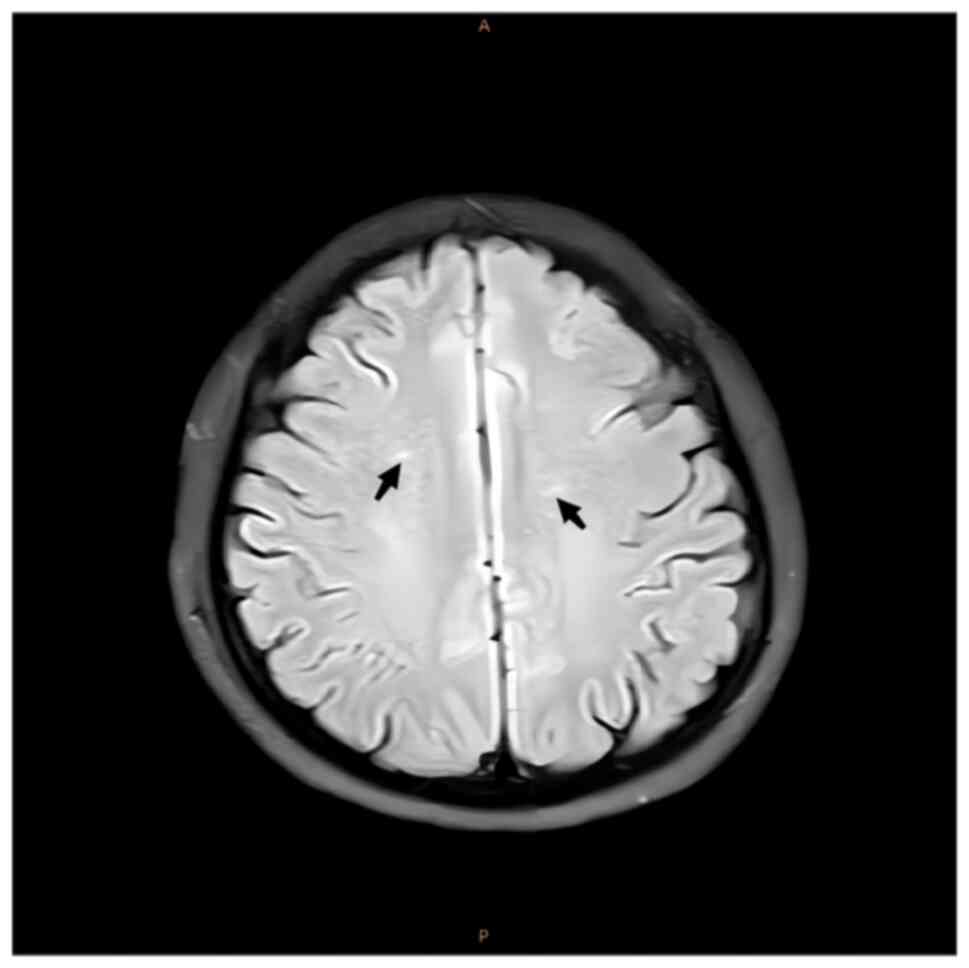

After 6 months of follow-up treatment, cranial MRI

images demonstrated that the symmetrical spot-like and short-stripe

abnormal signals in the centrum semiovale were reduced compared to

previous scans (Fig. 8). The Hcy

and serum vitamin B12 levels of the patient were also within the

normal range.

weakness, sensory ataxia and paraesthesia (11). In the present study, the patient's

lesions were mainly in the bilateral centrum semiovale as there was

a high signal in this region on T2 MRI and FLAIR. In the present

study, the lesions were symmetrical and perpendicular to the long

axis of the bilateral lateral ventricles, which is a characteristic

manifestation of SCD. These lesions are either directly or

indirectly related to the vitamin B12 deficiency observed in the

patient.